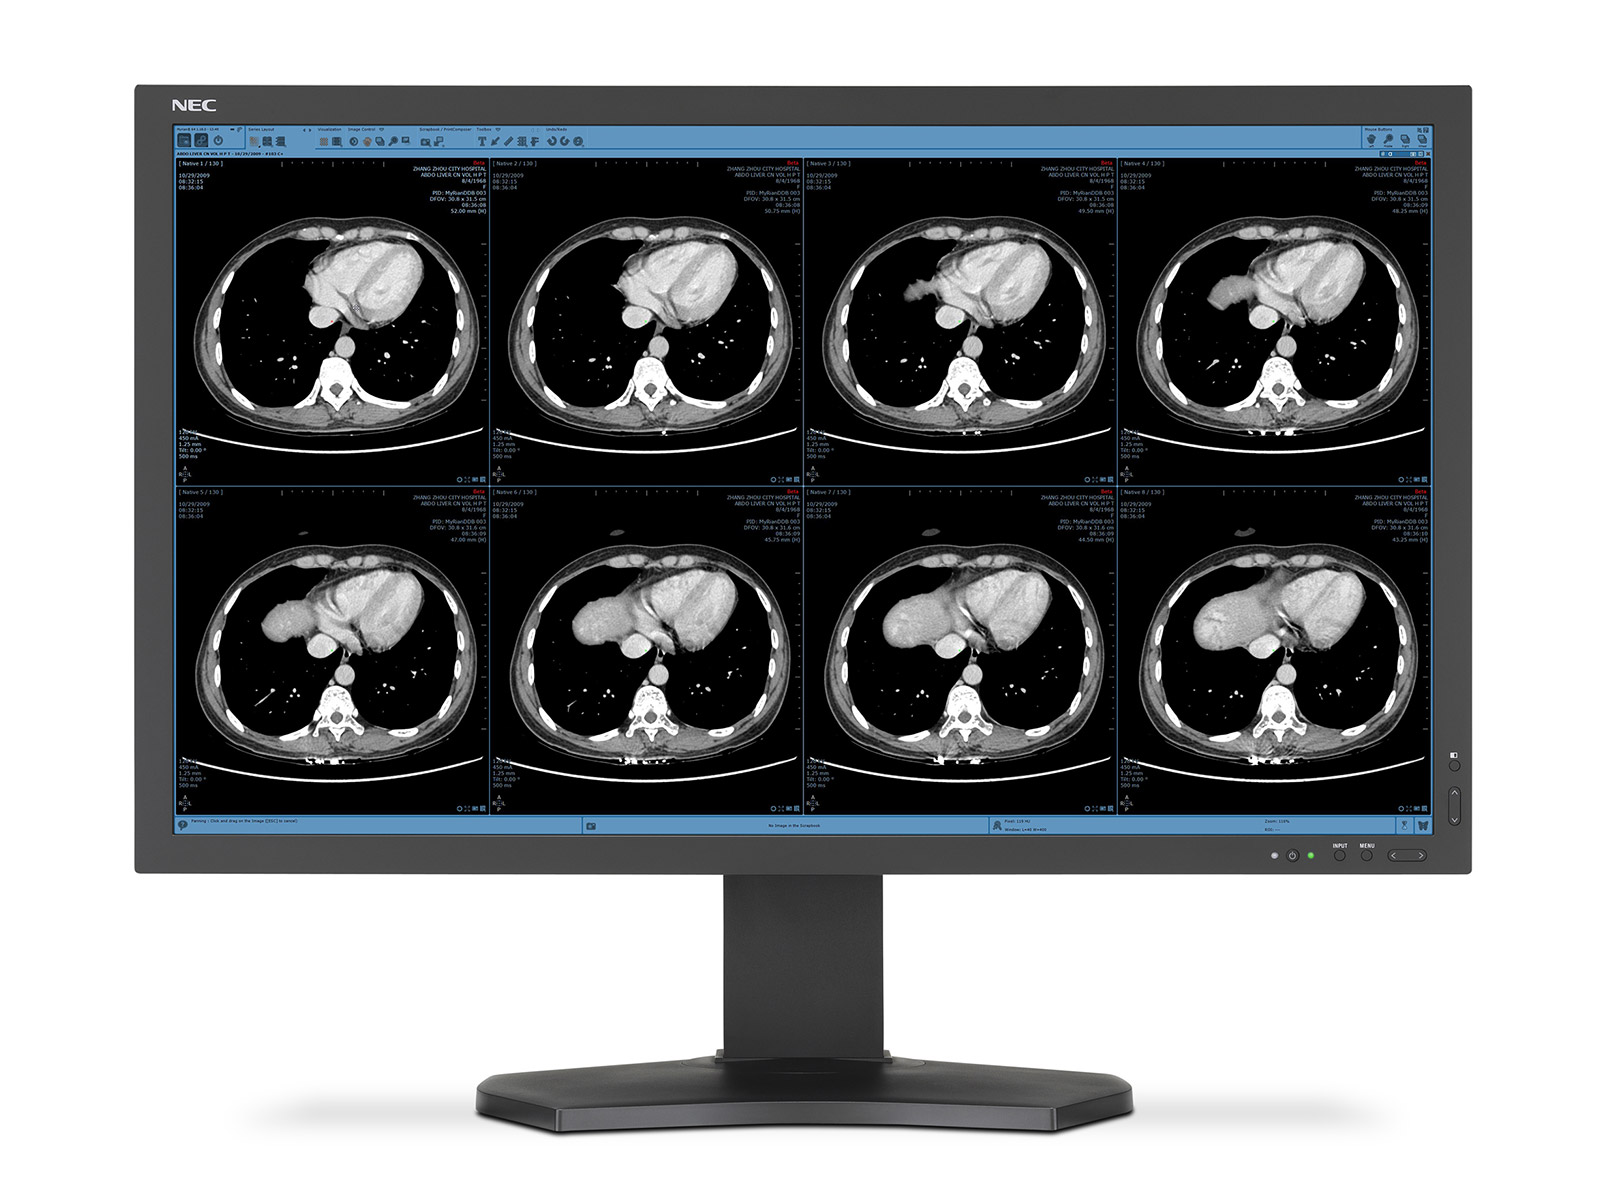

The Merian Iselin Hospital selected the NEC MultiSync® X841UHD 8MP monitor featuring a screen diagonal of more than two metres and DICOM mode for clinical review of x-ray images for use in the MDT room. An NEC MultiSync MD322C8, with the same resolution as the large-format display, is used as an input monitor for the radiologists.

The extreme detail achieved with the UHD resolution display permits more precise diagnoses and allows extremely low viewing distances. Medical image data is reproduced correctly thanks to precise calibration and DICOM mode. “Black is really shown as black, just like white is really white on the screen”, says Dr. Egelhof with delight. A semi-matt surface restricts the effect of reflections on the screen.

The diagonal dimensions of more than two metres allow several images to be shown alongside each other for direct comparison. The sheer size permits groups of up to 10 people to gather in front of the screen with unrestricted views. Thanks to the high display brightness, images remain stable regardless of the ambient room lighting. Whilst in operation, the monitor does not emit any audible sound, therefore concentration is not impaired, even in larger groups or sensitive meeting situations.

Thanks to the wide variety of connection options, several signal and cable types allow a flexible choice of playback sources. Picture Archiving and Communication System (PACS) software permits the communication of findings and distributes image data to the connected peripheral devices. The monitor supports the Visus viewer used and can thus be integrated in the solution without any problems. The Radiology Information System (RIS) from medavis is used for the workflow management.

“The Merian Iselin Hospital offers its customers and patients best service and highest quality. Therefore, the requirements which the hospital imposes on itself, also apply to the technical equipment”, says Christoph Kreutner, Technical and IT Manager of the hospital. “The discussion of the x-rays is now possible for the first time at the highest level, as the image can now be shown in the same quality and grade as on the diagnostic monitor.”

“A good diagnostic monitor says more than 1000 diagnostic words”, says Dr. Egelhof. “With the use of the new meeting room resolution, the diagnostic work could be visualised and thus the credibility of the findings could be increased, as the lesions are shown in a better and more precise manner.” This leads to less uncertainty for all involved and increases productivity both in radiology itself as well as referring physicians and other incorporated medical specialisations.